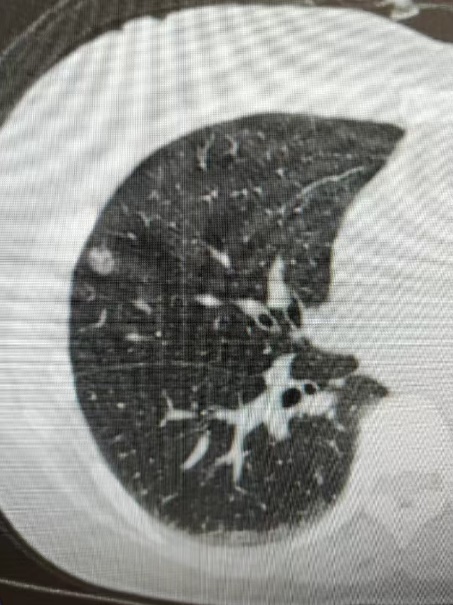

有一名女性患者,因咳嗽、咳痰40余天来院就诊,行胸部CT提示:右肺上叶病灶,不排除肺癌可能。为进一步明确诊断,予以充分评估后,在CT引导下行经皮肺穿刺活检术,病理结果显示:(右肺)肺泡上皮异型增生,局灶结构紊乱,考虑腺癌,建议免疫组化六项检查,为患者的后续精准治疗提供了依据。